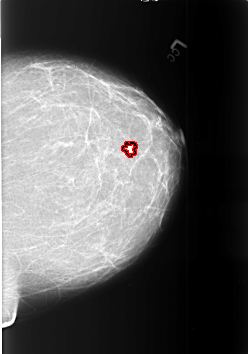

B_3372_1.LEFT_CC

LEFT_CC LINES 5664 PIXELS_PER_LINE 3960 BITS_PER_PIXEL 12 RESOLUTION 50 OVERLAY

FILE: B_3372_1.LEFT_CC.OVERLAY

TOTAL_ABNORMALITIES 1

ABNORMALITY 1

LESION_TYPE MASS SHAPE IRREGULAR-ARCHITECTURAL_DISTORTION MARGINS SPICULATED

ASSESSMENT 4

SUBTLETY 2

PATHOLOGY MALIGNANT

TOTAL_OUTLINES 1

BOUNDARY